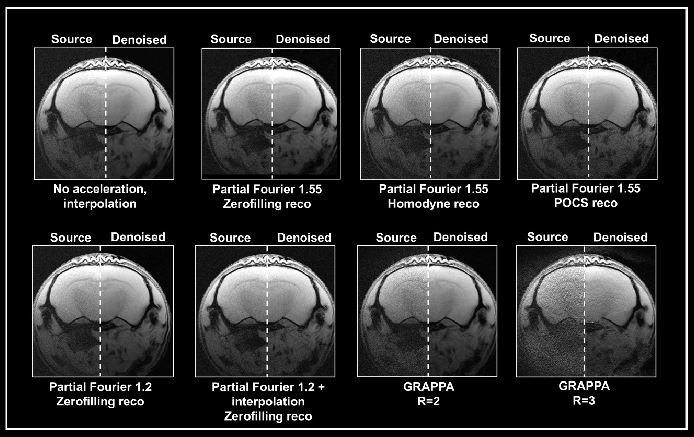

Ex vivo brain data were obtained with either partial Fourier or the multi-coil generalized auto-calibrating partial parallel acquisition (GRAPPA) approach (Fig. 5). Data obtained without acceleration served as a reference. Acceleration translated into an up to 3-fold decrease in acquisition times compared to the protocol when no averaging was used.

Figure 5. Denoising of accelerated brain data. Ex vivo T1-weighted FLASH data of a fixed mouse head were acquired at 9.4 Tesla. Data were either acquired with no acceleration, with partial Fourier (in Read), partial Fourier and interpolation (1.35 in Read and Phase), or with multi-coil parallel imaging technique GRAPPA. For GRAPPA, an acceleration factor (R) of 2 and 3 was chosen, respectively. Partial Fourier images were reconstructed either with zerofilling, homodyne, or POCS, as indicated. All images are shown with no denoising (Source) and after denoising (Denoised) with a Strong network, applying a pre-denoising level of 50% and denoising level of 70%. Image Credit: Bruker BioSpin Group

A denoising level of 70% led to more residual noise in data obtained with a partial Fourier 1.55 compared to data obtained without acceleration. The effect was most significant in homodyne-reconstructed data and lower in zero-filled data. Furthermore, denoising of these accelerated datasets led to image blurring, which was also most robust in homodyne-reconstructed images and lowest in images that were reconstructed with zero-filling.

Obtaining images with partial Fourier 1.2 led to less residual noise and normal image appearance when denoised with 70%. Denoising was ineffective, however, when combining a partial Fourier with interpolation (1.35 in Read and Phase) with the source and the denoised image having similar appearance.

Grappa acceleration led to noisier images than in acquisition with partial Fourier. Reconstructing the obtained data with the denoising algorithm removed noise from the GRAPPA image obtained with an acceleration factor 2.

However, the noise is not fully removed in the image obtained with an acceleration factor 3. Furthermore, reconstruction artifacts and loss of tissue contrast unrelated to the denoising reconstruction are visible.

This demonstrates that the algorithm may be unable to work with data that has a noise characteristic different from the noise that the networks have been trained with (i.e., without acceleration and interpolation). Yet, the outcome is dependent on the selected acquisition and reconstruction parameters.